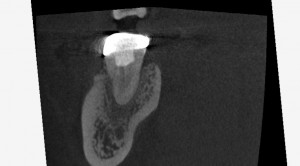

3カ月後、かなり骨の再生が認められます。

仮歯も問題なさそうだったので被せることにしました。

破折が怖いのでフルジルコニアをいれました。

いい感じですね。